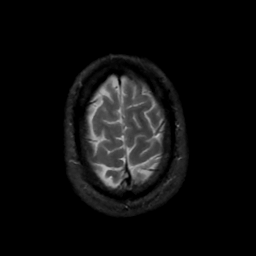

MR Study #15, June 9, 1991 -- Slice #44

[Home][Help][Clinical][Tour 1][Tour 2] Slice 44